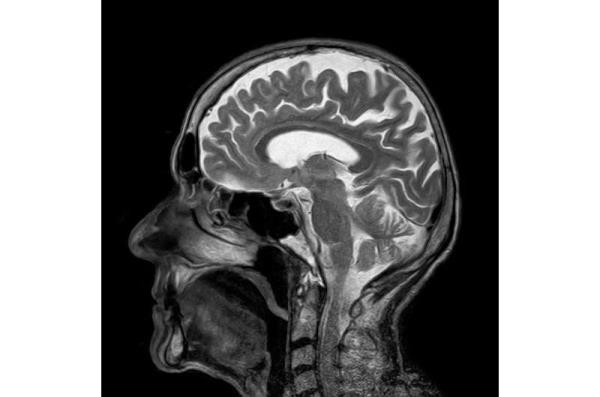

约翰霍普金斯大学开发了一种名为DeepSTI的新算法,可以绘制出非常详细的3d地图,显示人脑组织的磁化率。来源:约翰霍普金斯大学

该团队的新算法从核磁共振扫描中获取数据,并生成大脑磁化率的高分辨率3D地图。研究人员说,这项技术的关键进步在于,它能够使用比以前更少的扫描来测量髓磷脂和铁等脑组织来源。捕捉这些组织的变化有助于确定神经系统疾病的类型、阶段或进展;例如,他们的算法生成了一个重建,以可视化多发性硬化症患者的髓磷脂变化,使用从一个头部方向扫描收集的数据。